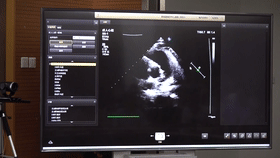

5G遠(yuǎn)程會(huì)診現(xiàn)場,西安國際醫(yī)學(xué)中心心內(nèi)科張衛(wèi)澤主任、超聲科陳姍姍主任打開4K高清顯示器,屏幕上立刻出現(xiàn)了商洛國際醫(yī)學(xué)中心的B超畫面,一位醫(yī)生正在為患者做心臟B超,隨著探頭的轉(zhuǎn)動(dòng),超聲機(jī)器上的畫面清晰可見,雖然兩家醫(yī)院相距一百多公里,但畫面流暢,沒一點(diǎn)拖沓。

“真的太棒了”張衛(wèi)澤表示,“沒有延時(shí)與卡頓,清晰的好像在一個(gè)房間內(nèi)進(jìn)行病歷討論”。陳姍姍非常興奮,直呼很震撼。她告訴筆者,“以前做遠(yuǎn)程會(huì)診,經(jīng)常遇到畫面和聲音不在一個(gè)頻道、畫面模糊等情況,遇到疑難病歷只能將影像拷下來回去研究,現(xiàn)在好了這些問題都將一次性解決。”